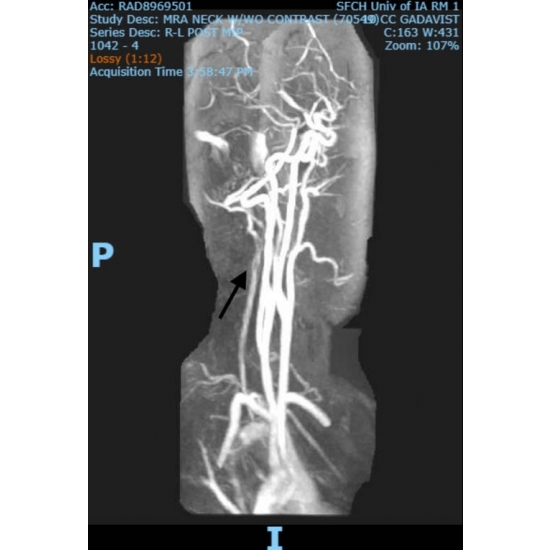

| Do Not Jump To Conclusions - Neck Pain After A High Ropes Course Mishap - Page #3 | |||